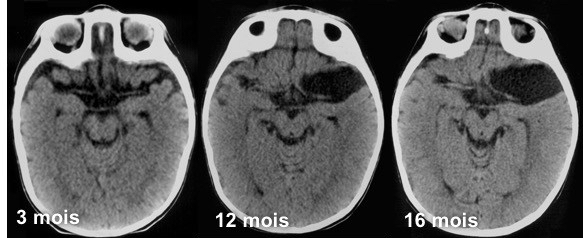

Alors qu’ils sont de loin les kystes arachnoïdiens plus fréquents en post-natal, ils sont rares (et différents) en diagnostic anténatal. il s’agit donc très probablement de kystes acquis, c’est une pathologie développementale, comme le suggèrent certaines observations comme celle ci-dessous.

on note parfois rétrospectivement une ascension du périmètre crânien dans la petite enfance qui suggère une date pour l’apparition du kyste. par ailleurs, il existe une prédominance des garçons (2 cas sur 3) et du côté gauche (2 cas sur 3 également). parfois les kystes arachnoïdiens sylviens sont associés à une inflation globale des espaces méningés et ventriculaires et une augmentation du PC, qui suggère une trouble diffus de l’hydrodynamique intra-crânienne.